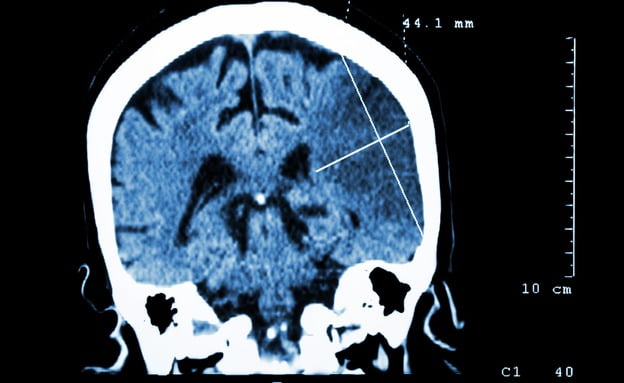

Après l’hospitalisation de l’ancien Président en raison d’un accident vasculaire cérébral (AVC) massif, le Professeur Israël Steiner, chef du service de neurologie à l'hôpital Beilinson explique ce qu’est l’AVC, quelles en sont les causes et pourquoi l’âge avancé affecte les chances de récupération.

Steiner explique qu’AVC signifie interruption de l'approvisionnement en sang vers les tissus du cerveau. Cela peut être causé par trois raisons: la première raison est la formation de caillots sanguins, le plus souvent à cause de l'athérosclérose. Lorsque le caillot atteint des dimensions telles qu’il obstrue les vaisseaux sanguins, il se produit une interruption de l'approvisionnement en sang. Sans intervention pour ouvrir le vaisseau qui assure alimentation du cerveau en sang et en oxygène au cerveau, ce tissu meurt.

La dernière option peut être causée par l'hypertension, une tendance aux hémorragies ou un dysfonctionnement causé par une prise de médicaments, entraînant une hémorragie cérébrale. Cela peut être considéré comme un AVC mais ce cas présent résulte d’une masse de sang accumulé dans les tissus.